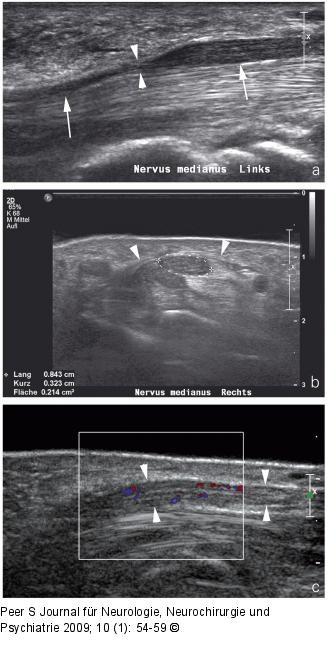

Abbildung 3a-c: Neruvs medianus (a) Sonographischer Längsschnitt durch den Nervus medianus (Pfeile) am distalen Unterarm eines Patienten mit Karpaltunnelsyndrom: Abrupter Kalibersprung (Pfeilspitzen) im Verlauf unter dem Ligamentum carpi transversum. (b) Sonographischer Querschnitt durch den Nervus medianus bei einem weiteren Patienten mit Karpaltunnelsyndrom: Deutliche Auftreibung des Nervs im proximalen Verlauf unter dem Ligamentum carpi transversum (Pfeilspitzen) mit einer Querschnittsfläche von 0,21 cm2 (Normwert bis 12 cm2). (c) Sonographischer Längsschnitt (selber Patient) durch den aufgetriebenen Nervus medianus (Pfeilspitzen) mit Darstellung multipler Farbsignale, hinweisend auf eine reaktive Entzündung. |